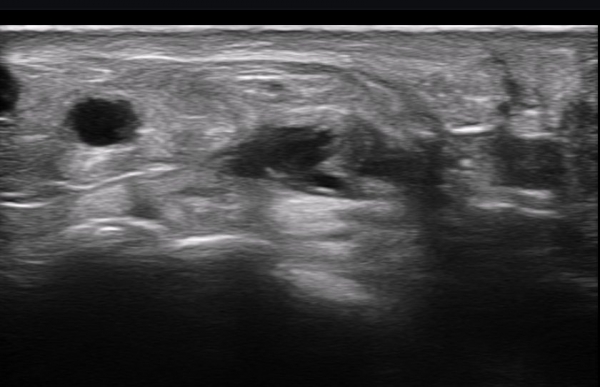

ÃÊÀ½ÆÄ ¼Ò°ß : ºñº¹½Å°æ Ⱦ´Ü¸é°Ë»ç¿¡¼­(»çÁø 1~13) ºñº¹½Å°æÀÇ Àú¿¡ÄÚ ºÎÁ¾°ú ´Üºñ°ñ°Ç³» ³¶Á¾¼º º´º¯ÀÌ °üÂûµÈ´Ù.

ºñº¹½Å°æ Á¾´Ü¸é°Ë»ç(»çÁø 14, 15)¿¡¼­ ºñº¹½Å°æÀÇ Àü¹ÝÀûÀÎ Àú¿¡ÄÚ ºÎÁ¾°ú ºñº¹½Å°æ ½ÉÃþÀ¸·Î ´Üºñ°ñ°Ç³»

³¶Á¾¼º º¯º¯ÀÌ °üÂûµÈ´Ù.